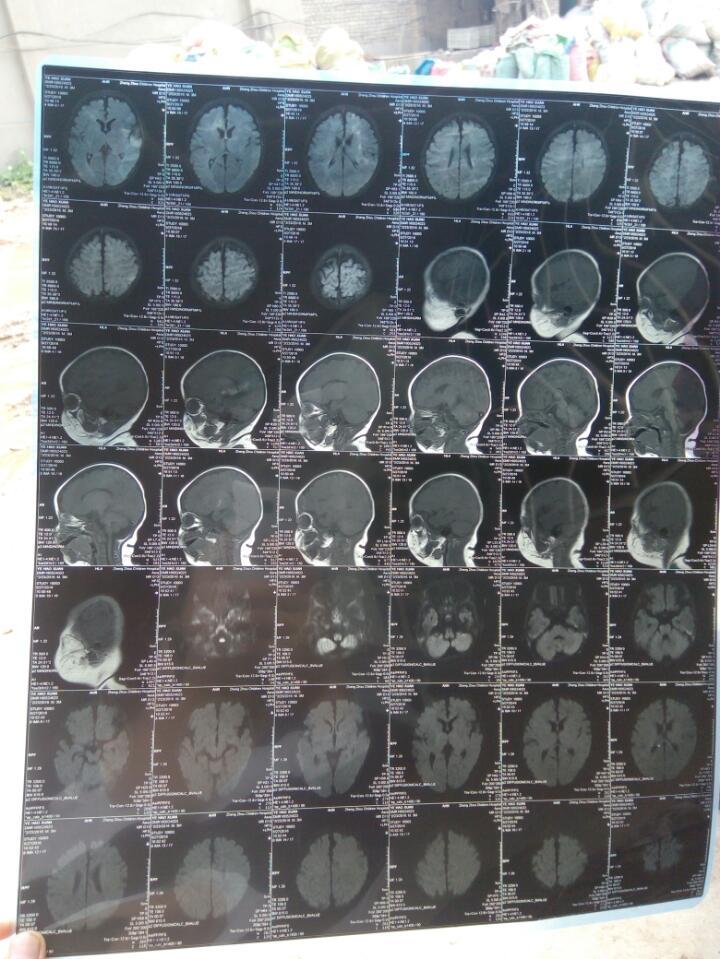

我家宝宝早产一个月,生下来缺氧,有轻度脑损伤,在保温箱里用药一个疗程神经节苷脂,出院在家用了一个疗程,三个月去郑州市儿童医院复查,做磁共振检查说是白质髓鞘发育落后于3月龄儿,肌张力高,也可以听得到,就是听的慢,也知道追物,头也可以抬起来,也会笑,医生让我们用那个鼠神经生长因子,我们没用,用的还是神经节苷脂,用了4针,相等5个月的时候再去复查一下,可以吗?现在用4针药有用吗?